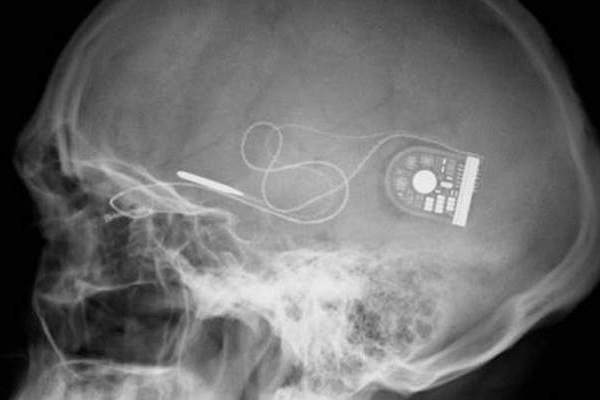

DARPA razvija neurološki čip

DARPA - agencija Ministarstva obrane SAD-a radi na novim tehnologijama za vojsku SAD-a. S vremenom, dobar dio materijala završi u privatnim rukama, poput interneta ili GPS sustava.

Stručnjaci u DARPA-i trenutno rade na posebnom programu koji za svrhu ima u ljudski mozak ubaciti malene implantante koji bi potom direktno komunicirali s neurološkim sustavom. Na ovaj način, bez ikakvih medikamenata ili psiholoških programa mogla bi se izmijeniti struktura mozga te gotovo trenutno izliječiti brojne akutne ali i kronične bolesti, poput depresije, PTSP-a i mnogih drugih.